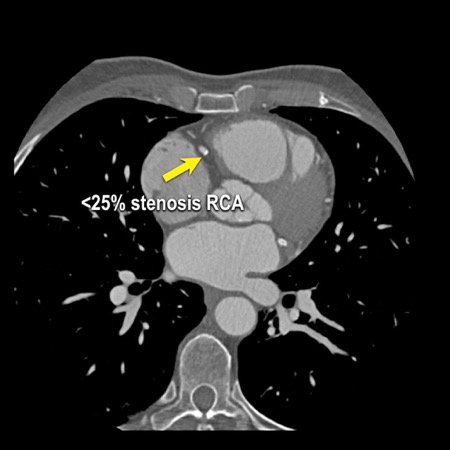

case 1 – CAD-RADS 2/P1

First, scroll through the scan.

Not all images are included. Some images without any abnormalities are skipped

from the series.

How would you describe the findings on the coronary CTA?

The findings are:

- Agatston score of

this patient was 14 (P1). Please, also note the calcification of the aortic valve. - Some partially

calcified and calcified plaques are present in the LAD with mild stenosis

(25-49%). - Calcified-plaque in

the LCX causing minimal stenosis (<25%). - Non-calcified

plaque in the distal RCA causing minimal stenosis (<25%). - This patient classifies

as CAD-RADS 2/P1, which means no further workup is needed.